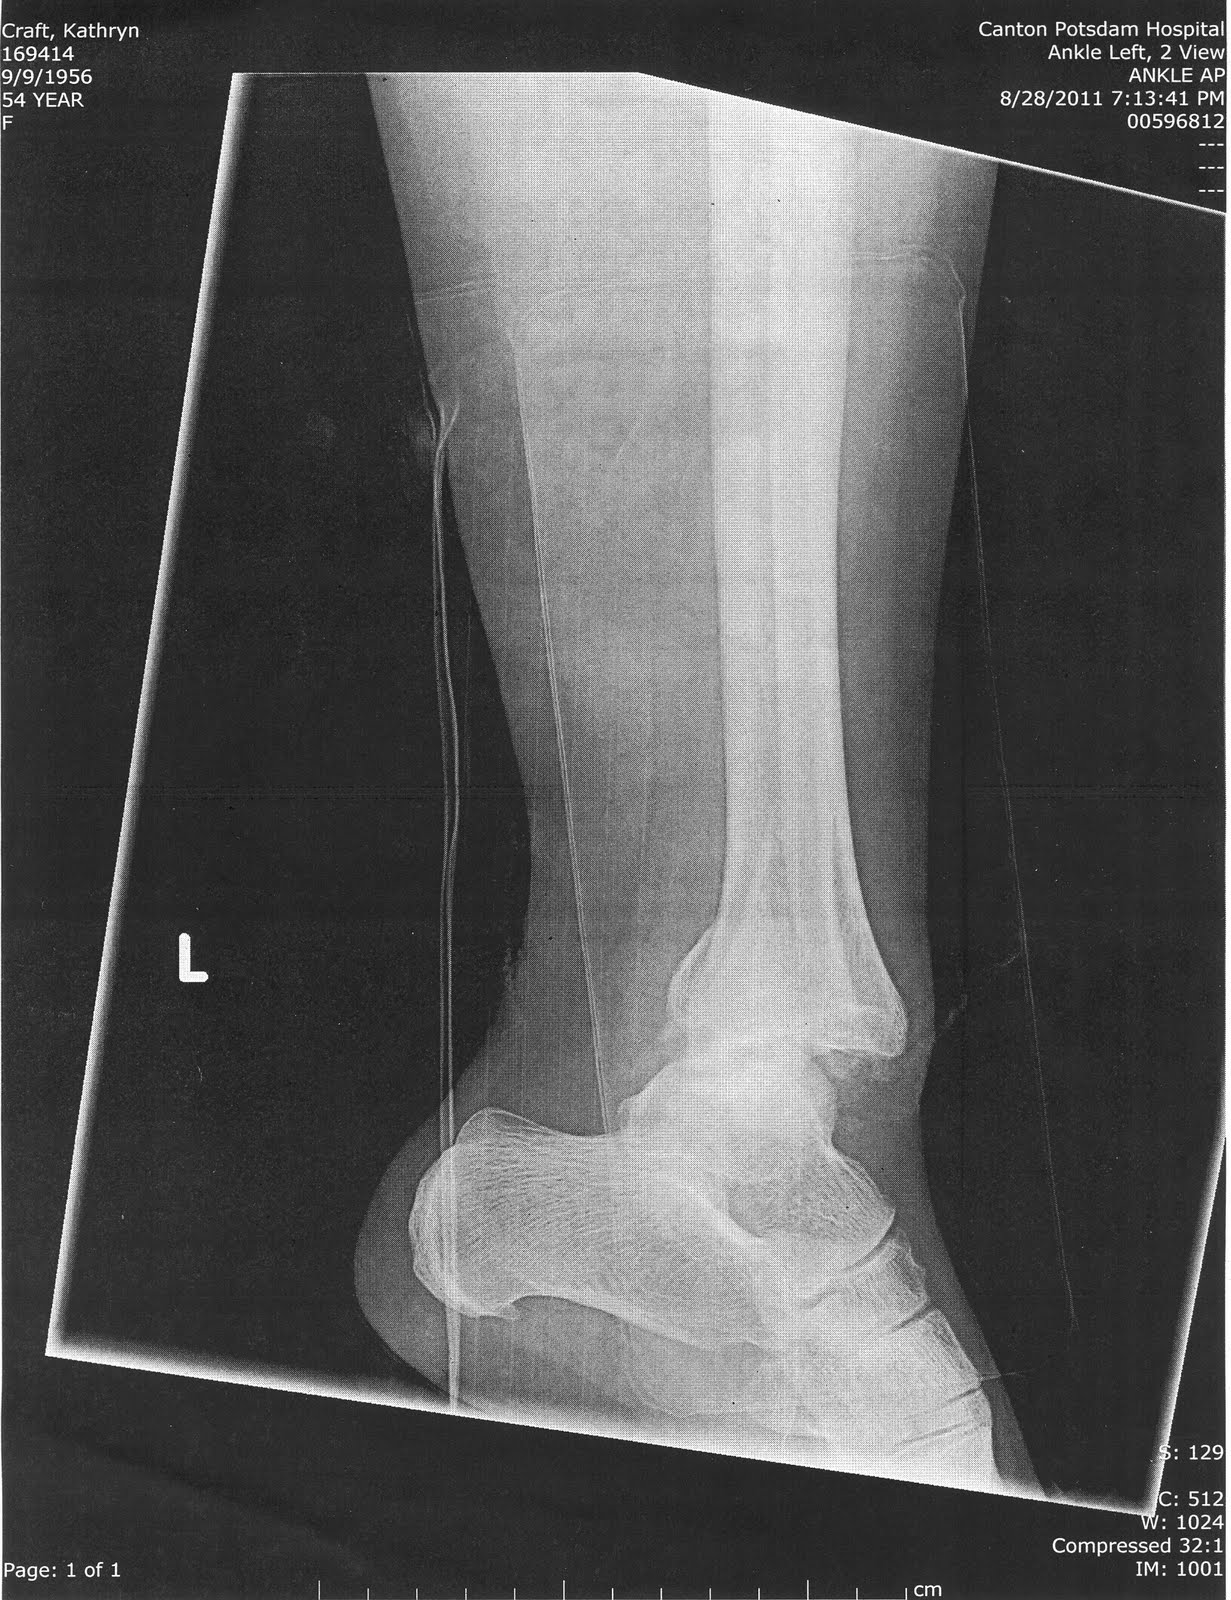

Ankle fracture essay in 2021

Ankle fracture essay image This picture representes ankle fracture essay.

The diagnosis of letter a fracture in the wrist or ankle joint is made from 2 standard photography views taken atomic number 85 right angles to each other. As broadening of the articulatio talocruralis mortise by 1 mm decreases the contact area of the tibiotalar cooperative by 42%, this could lead to instability and thu early osteoarthritis of the tibiotalar common.